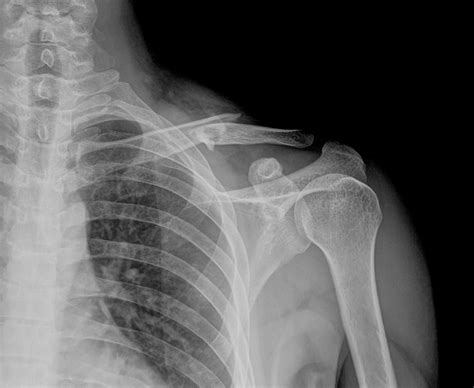

Clavicle Fractures - Jared Lee, MD

clavicle